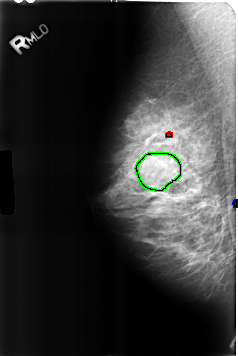

FILE: B_3226_1.RIGHT_MLO.OVERLAY

TOTAL_ABNORMALITIES 3

ABNORMALITY 1

LESION_TYPE CALCIFICATION TYPE COARSE DISTRIBUTION N/A

ASSESSMENT 2

SUBTLETY 3

PATHOLOGY BENIGN_WITHOUT_CALLBACK

ABNORMALITY 2

LESION_TYPE MASS SHAPE OVAL MARGINS CIRCUMSCRIBED-OBSCURED

PATHOLOGY BENIGN

ABNORMALITY 3